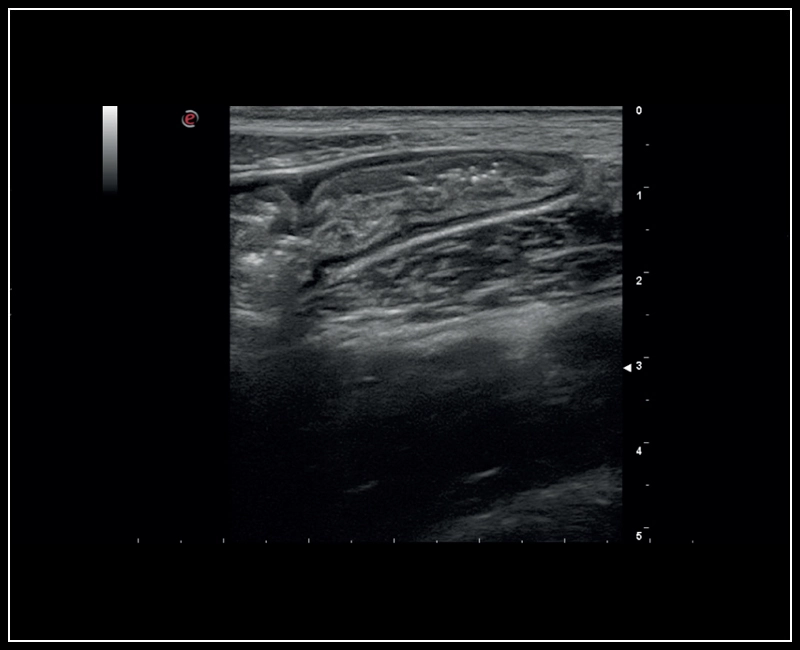

MyLab™9 Platform - High resolution imaging in testis

MyLab™9 Platform - High resolution imaging in testis